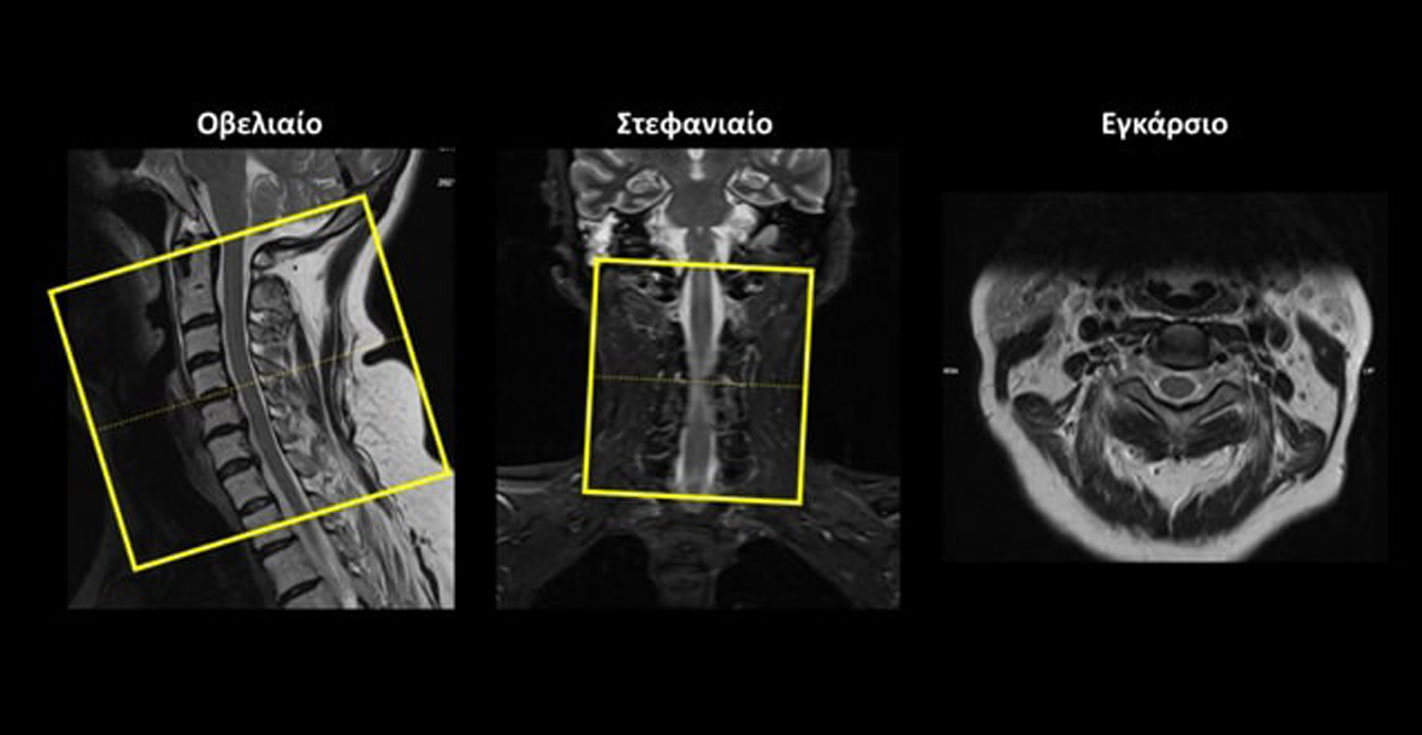

Οβελιαίο (Sagittal): οι οβελιαίες τομές σχεδιάζονται παράλληλα με τον νωτιαίο μυελό στο στεφανιαίο επίπεδο. Οι τομές περιλαμβάνουν μόνο τον νωτιαίο μυελό, από τα δεξιά έως τα αριστερά.

Εγκάρσιο (Axial/Transversal) στην ΑΜΣΣ: οι εγκάρσιες τομές σχεδιάζονται κάθετα στον νωτιαίο μυελό, τόσο στο οβελιαίο όσο και στο στεφανιαίο επίπεδο. Οι τομές πρέπει να περιλαμβάνουν ολόκληρο τον αυχενικό νωτιαίο μυελό, από το ινιακό τρήμα έως το επίπεδο Α7-Θ1.